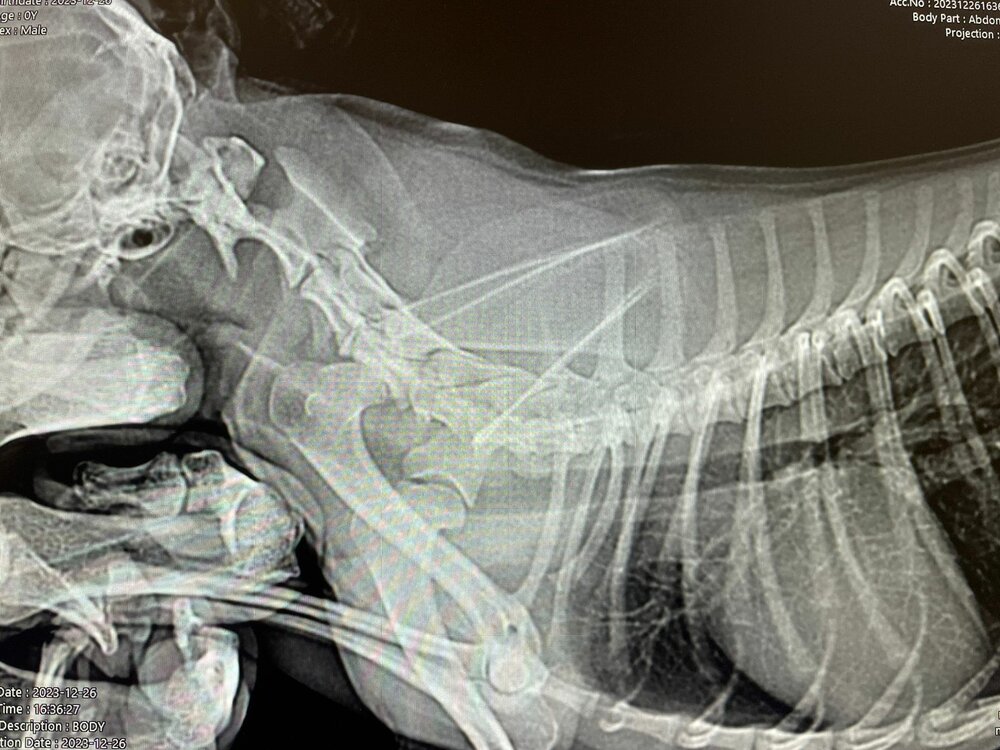

Ребята помогите, у кого был такой диагноз. Собака болеет уже вторую неделю. Врачи ставили разные диагнозы. Лечили нам и уши и живот, пока не доехали в другой город. Диагноз дискоратия грудного отдела. Назначили уколы флексопрофен. Сегодня последний укол, делаем их на ночь. Под утро начинает скулить. Уже и не знаем что делать. Может кто сталкивался, как лечили?

• 1_IMG-20231226-WA0041.jpg

Чихуахуа (IMG-20231226-WA0041.jpg)

149,1 KB · Просмотры: 156